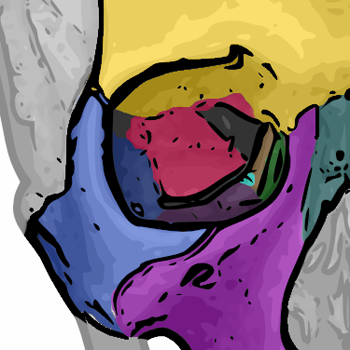

Das Auge ist in der knöchernen Augenhöhle, auch Orbita genannt, eingefasst(4). Dies ist eine nahezu viereckige pyramidenförmige Höhlung im Frontalbereich des Schädels (2). Da der Schädel eines Menschen aus mehreren getrennten Knochen besteht, welche im Laufe des Heranwachsens zu einem festen Knochen zusammenwachsen (TODO: QUELLE für mehr Infos: https://flexikon.doccheck.com/de/Sch%C3%A4delknochen ## 5. Schädelwachstum), bildet sich die Augenhöhle aus Anteilen von insgesamt sieben verschiedenen Knochen (2). In Abbildung XY sind diese Knochen farbig dargestellt und benannt. Die sieben Knochen sind:

- Jochbein (Os zygomaticum) in blau

- Stirnbein (Os frontale) in gelb

- Tränenbein (Os lacrimale) in grün

- Oberkiefer (Maxilla) in violett

- Siebbein (Os ethmoidale) in braun

- ein kleiner Teil des Gaumenbeins (Os palatinum) in hellblau

- Keilbein (Os sphenoidale) in rot

! Quelle: Wikipedia

TODO: Vielleicht finden wir noch ein besseres Bild, oder ein zweites, das etwas schräg hieneinsieht, damit man Tränenbein und Siebbein besser erkennen kann.

Begrenzungen der Augenhöhle (alles Quelle 4)

Dabei wird die Augenhöhle in vier Begrenzungen einteilen: Das Orbitadach bildet die obere und hintere Begrenzung der Augenhöhle und wird vom Stirnbein (gelb) und Keilbein (rot) gebildet. Der Orbitaboden begrenzt die Augenhöhle nach unten und besteht hauptsächlich aus dem Oberkiefer (violett) und teilweise aus dem Jochbein (blau). Die laterale Orbitawand begrenz die Augenhöhle von der Körpermitte aus gesehen nach außen (links bzw. rechts). Sie wird vor allem aus dem Jochbein (blau) und teilweise aus dem Keilbein (rot) gebildet. Zuletzt begrenzt die sehr dünne mediale Orbitawand die Augenhöhle zur Körpermittel bzw. Nase hin und wird aus dem Oberkiefer (violett), dem Tränenbein (grün), dem Siebbein (braun) und Teilen des Stirnbeins (gelb) sowie des Keilbeins (rot) gebildet.